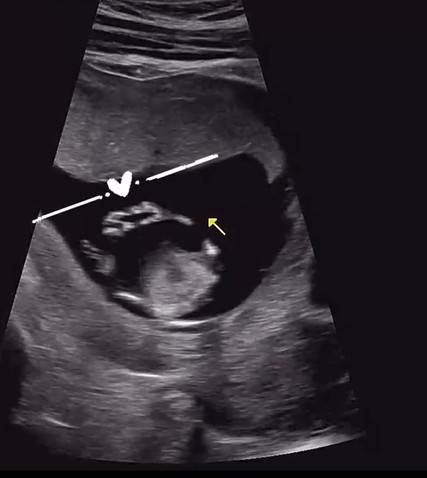

이와 함께 초음파 사진도 공개했다. 박가령은 "벌써 하트를 하고 있는 아가. 많은 응원과 격려 부탁드려요 #임신 #임밍아웃"이라고 덧붙였다.

박가령은 "벌써 하트를 하고 있는 아가. 많은 응원과 격려 부탁드려요 #임신 #임밍아웃"이라고 덧붙였다.